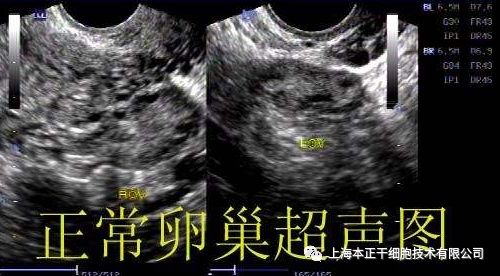

“对接受过治疗的卵巢的超声成像显示,与对照的卵巢相比,其尺寸明显增大。就目前完成治疗的参与者而言,她们可以很好地耐受这些操作,没有任何副作用的迹象。” Al-Hendy说道。